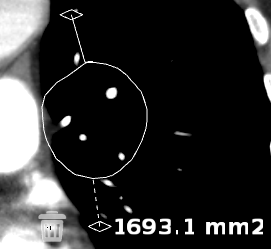

To obtain a free region measurement:

Select the

Free Region  icon

icon

Click on the region of interest

Drag on the mouse to encircle the area

Release the mouse button

To move the whole free region, select the upper

grab point  . To

extend areas of a free region, click on the desired area to reveal 3 grab

points. Selecting one of these grab points will extend the free

region to include a specific area.

. To

extend areas of a free region, click on the desired area to reveal 3 grab

points. Selecting one of these grab points will extend the free

region to include a specific area.